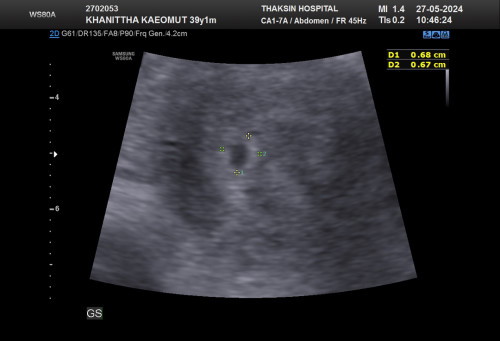

ท้อง5สัปดาแต่เจอถุง ตั้งครร ขนาด4สัปดา

ยังไม่เจอถุงไข่แดงเลยคะ ใครเคยเป็นแบบเราบ้าง ใจคอไม่ดีเลยคะ

ปกติค่ะ อายุครรภ์ยังน้อยมาก